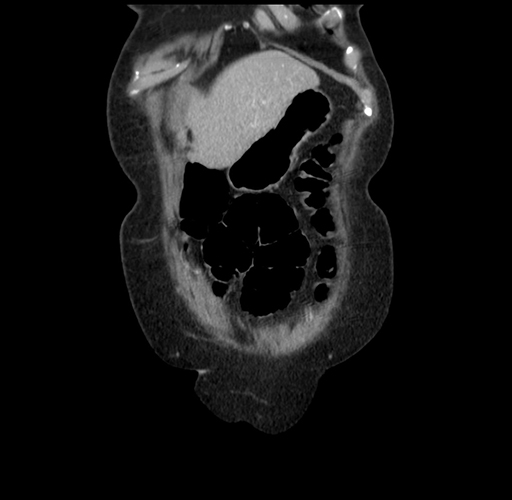

Pre-Chemo: Axial Venous